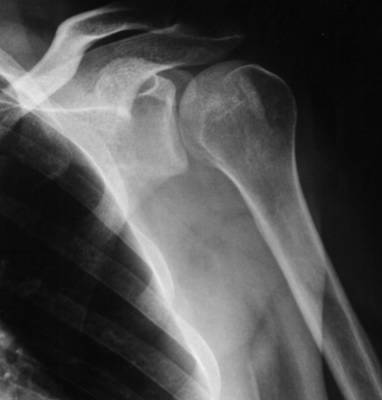

Vaig caure de mala manera, amb tant mala sort que s'em va "dislocar l'ombro", s'em va luxar l'espatlla (més correctament)

Al ambulatori em van dir que no em podien col·locar l'espatlla a lloc, perquè podria haver una fractura i que m'havien de fer radiografies per comprovar-ho.

Bueno, al final em van fer la corresponent radiografia, instantàniament em van fer asseure a una cadira de plàstic amb el braç penjant per fora del espatller.

Placa per comprovar que tot esta a "puestu" i cap a caseta.

Radiografia, cadira de plàstic, crock, un altre radiografia, i cap a caseta un altre cop.

Podeu comparar les dues radiografíes: